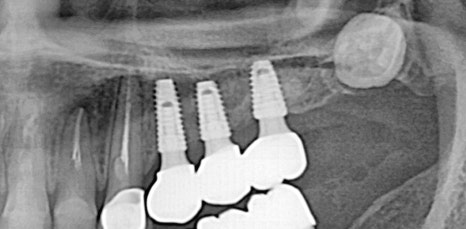

임플란트는 치아가 상실된 자리에 뿌리 역할을 하는 픽스처를 잇몸에 심어주고 지대주와 크라운을 연결하는 방법으로 주변 치아와 잇몸에 손상을 주지 않았어요. 또한 자연치아와 매우 유사해 심미적으로도 좋으며 저작력과 고정력이 자연치아의 80%까지 회복할 수 있어 기능적인 면에서도 장점이 많았어요. 비용적인 부분이 틀니나 브릿지 보다 부담이 되긴 하지만 반영구적으로 오랜 시간 사용할 수 있다는 점이 장기적으로 보면 더 효율적이라고 느끼시는 분들이 많으셨어요.

하지만 임플란트 시술을 튼튼하고 안전하게 하기 위해서는 무엇보다 잇몸뼈의 양, 두께 즉, 잇몸 상태가 매우 중요한 부분이었어요. 뿌리 역할을 하는 픽스처의 길이는 다양한 사이즈가 있지만 평균적으로 최소 8mm 이상이므로 잇몸 뼈의 길이가 8mm가 되지 않는 상태로 임플란트를 식립하게 된다면 픽스처가 잇몸을 뚫고 나가게 되어 구멍이 생기고 고정이 되기 어려웠어요. 그렇기 때문에 잇몸 뼈의 양이 부족하면 뼈 이식을 동반한 임플란트 시술이 필요했어요.

특히 위쪽 어금니 쪽이 상실 되어 임플란트 시술을 진행해야 하는데 잇몸 뼈가 부족한 상태라면 추가적으로 상악동거상술을 함께 진행해야 했어요. 상악동이란 코 양옆에 위치하고 있으며 뼈 속에 비어 있는 공기 주머니로 두개골의 무게를 줄여주는 곳이었어요. 상악동은 아주 얇은 막으로 둘러 쌓여 있으며 상악 쪽의 잇몸 뼈가 부족한 상태로 임플란트를 식립 하게 된다면 상악동 막이 찢어지거나 천공이 생길 수 있었어요.

상악동에 천공이 생기게 된다면 염증으로 인해 부작용이 생길 수 있었어요. 그렇기 때문에 환자 개개인마다 크기와 위치가 모두 다른 상악동의 위치와 잇몸 뼈의 두께를 정확히 파악하는 것이 중요했어요. 정밀 검사 후 임플란트를 식립 하기에 잇몸 뼈의 양이 부족하다는 진단이 나오게 된다면 얇은 상악동 막을 들어올려 준 후 필요한만큼의 뼈 이식을 진행해 주는 방법이 상악동거상술이었어요.

신논현역임플란트에서 말하는 상악동거상술은 치조정접근법과 측방접근법인 두가지 방법으로 진행할 수 있었어요. 남아 있는 잇몸 뼈의 양에 따라 이식 해야 하는 양이 달라지고 그로 인해 상악동에 접근 하는 방법을 기준으로 두가지 방법은 나눠 지고 있었어요. 먼저 치조정접근법은 잇몸 뼈가 4-8mm 정도 확보 되었을 때 사용하는 방법으로 치아가 상실 된 위치의 잇몸에 작은 구멍을 뚫어 준 뒤 그 구멍을 통해 상악동 막을 들어 올린 후 뼈 이식을 진행하는 방법이었어요.